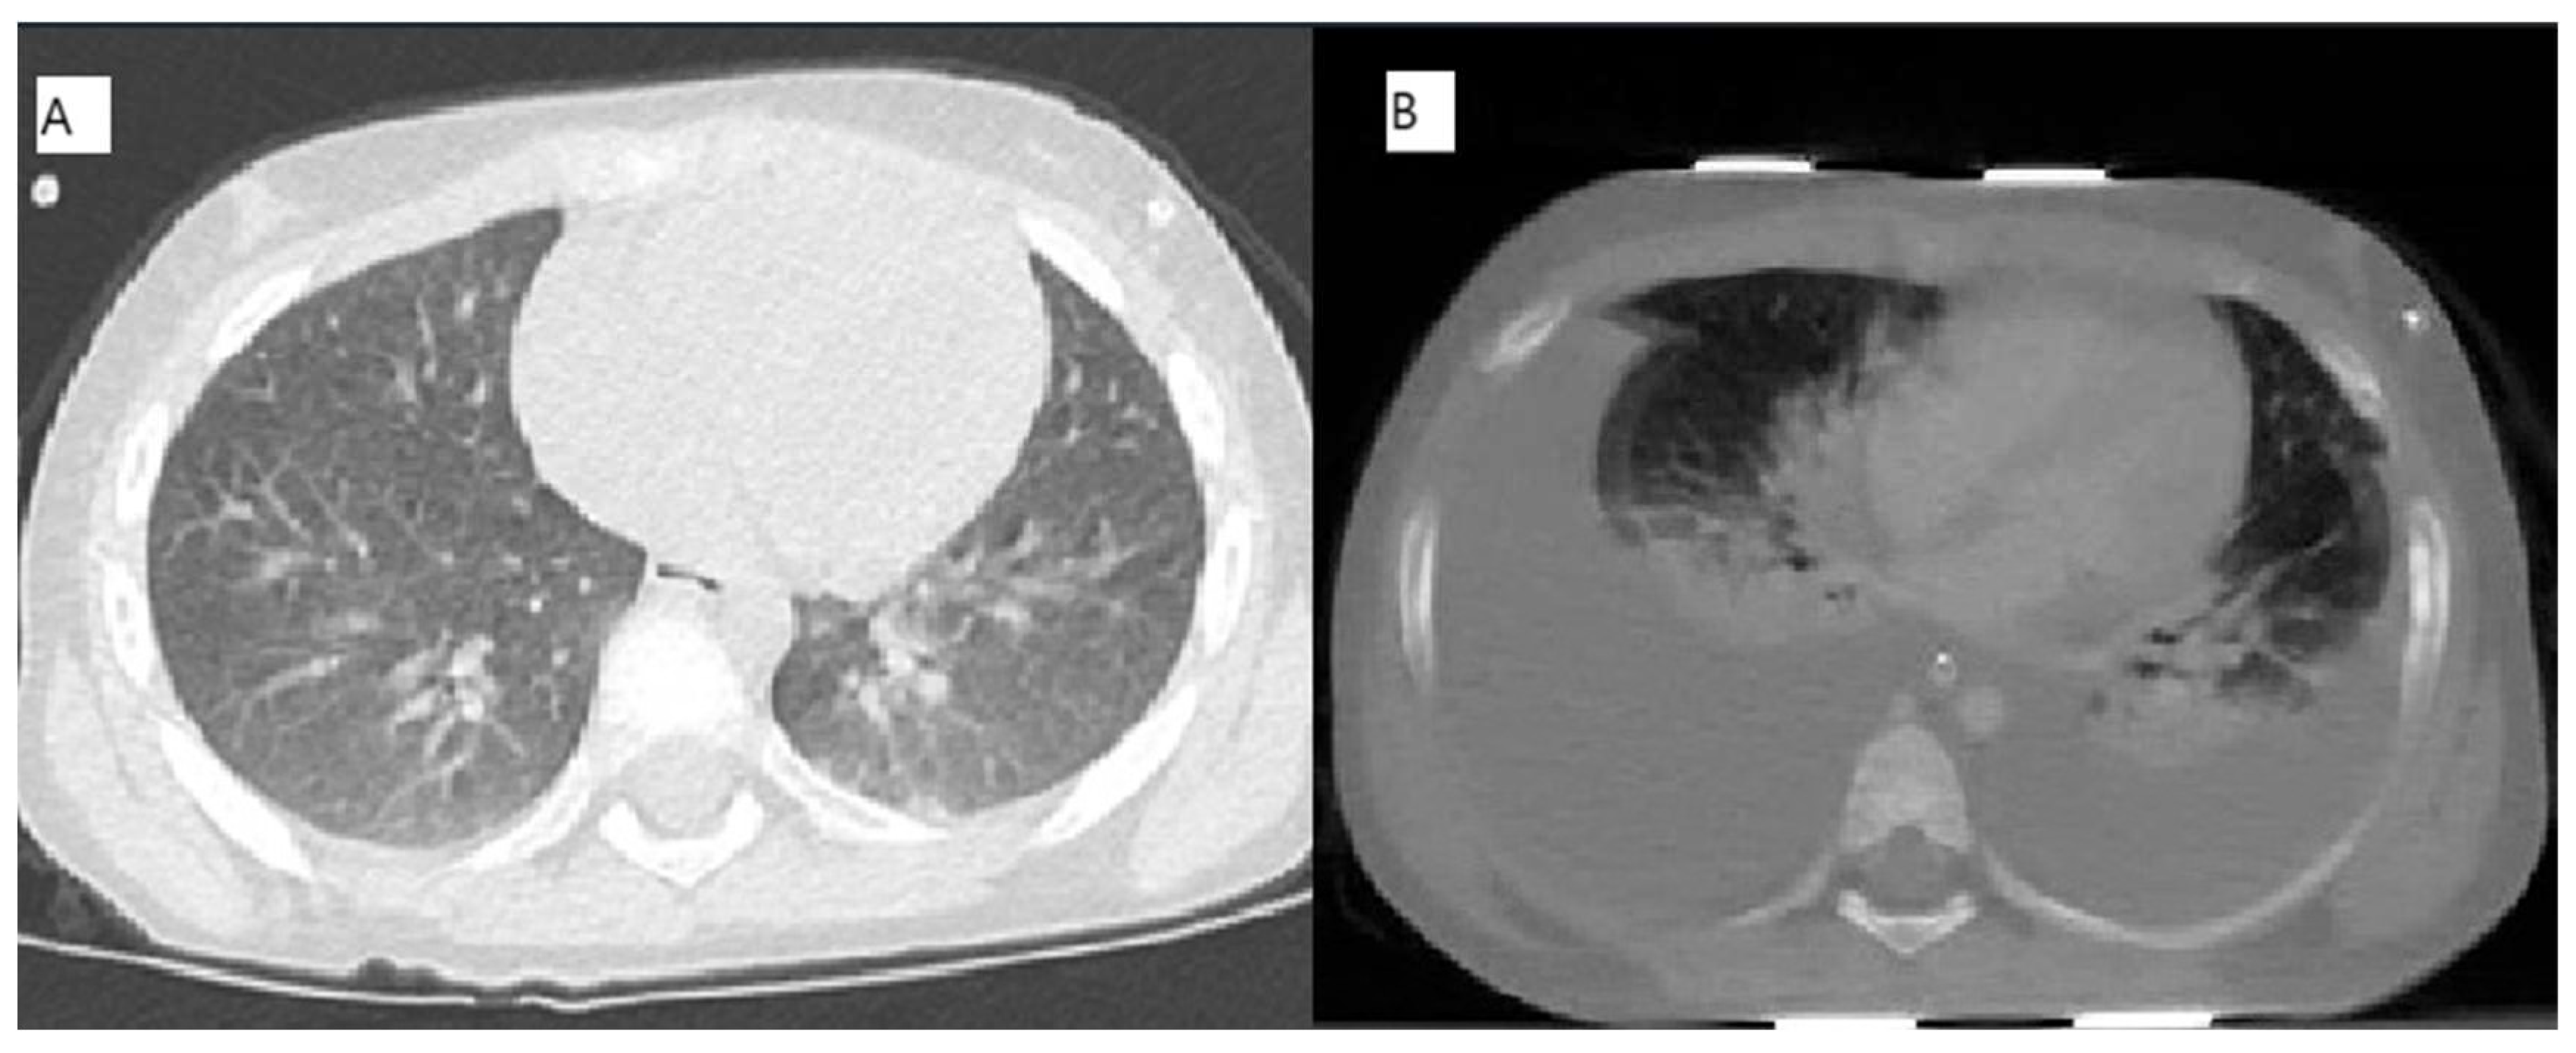

2.1. Case 1 [Unique Patient Number (UPN) 1069066]

2.2. Case 2 (UPN 1077926)